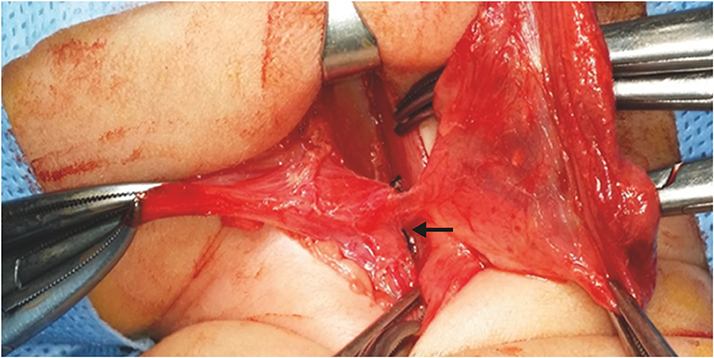

A newborn female infant, gestational age of 39+2 weeks, and 3.46 kg at birth was referred to our NICU due to a 7 cm sized left neck mass presented at birth. No significant medical history during antenatal care was noted. The baby arrived at our NICU 3 hours after birth and physical examination revealed a soft, tense, movable 7 cm long mass without signs of inflammation. Initial neck X-ray showed a 4.7×3.9 cm sized soft tissue density mass at left side of the neck containing round air density (Fig. 3A). With experience of patients with pyriform sinus cysts, gastric tube feeding was initiated from day 1. A sonographic study of the neck mass revealed findings consistent with pyriform sinus cyst, located at the medial side of the left carotid artery and extending to the posterior aspect of the left thyroid gland. The cyst was unilocular and contained isoechogenic debris. Esophagography showed a small tubular opacity from the left pyriform sinus adjacent to the air-filled cyst, suggesting a fistula (Fig. 3B). On neck magnetic resonance imaging (MRI), the fistula was not visualized but a cyst of homogeneous signal intensity without wall thickening or enhancement was visualized with air-fluid level, suggesting communication with the esophagus (Fig. 3C and D). On the 6th day of admission, pyriform sinus cyst resection and fistula ligation was done (Fig. 4). The size of the cyst was 7.0×3.5 cm on operation findings. Histological results of the dissected cyst were negative for malignancy and showed many benign squamous epithelial cells with some multinucleated histiocytes and mixed inflammatory cells. There was no intra-operative complication and the patient recovered uneventfully. Bottle feeding was initiated on postoperative day 7 and the patient was discharged 10 days after surgery.

Fig. 3

(A) Neck anteroposterior view and (C, D) T2-weighted neck magnetic resonance imaging of cystic mass with air (white arrow). (B) Fistulography shows a faintly opacified hairline tract (black arrows) originating from the left pyriform sinus.

Air bubbles in the inflammatory cavity of pyriform sinus tract may be due to production of air-forming bacilli or inhaled air from opening of pyriform sinus tracts [6]. These air bubbles may be noted on US, CT or MRI findings, and also on close observation of initial plain X-rays. In our first case, air bubble was not found on US but was visualized on the neck CT. At first, we assumed it to be air-fluid level within an abscess formed by anaerobic bacterial infection and treatment was targeted toward infection based on the assumption of complicated infected cystic hygroma. Earlier acknowledgement of the possibility of air inflow from an open sinus tract would have accelerated the process of correct diagnosis.